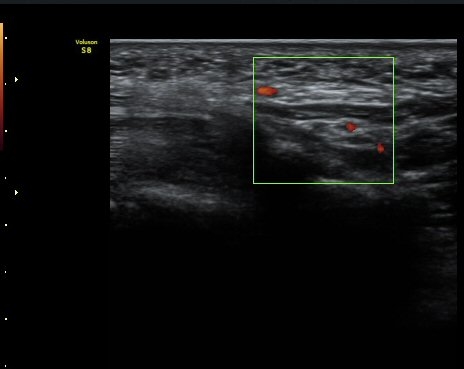

ÃÊÀ½ÆÄ °Ë»ç

¼Õ¹Ù´Ú ºÎÀ§ Á¤Á߽Űæ Á¾´Ü¸é°Ë»ç¿¡¼­ Á¤Áß½É°æ ½ÉºÎ¿¡ µÕ±Ù Àú¿¡ÄÚ Á¾±«°¡ °üÂûµÈ´Ù(»çÁø 1).